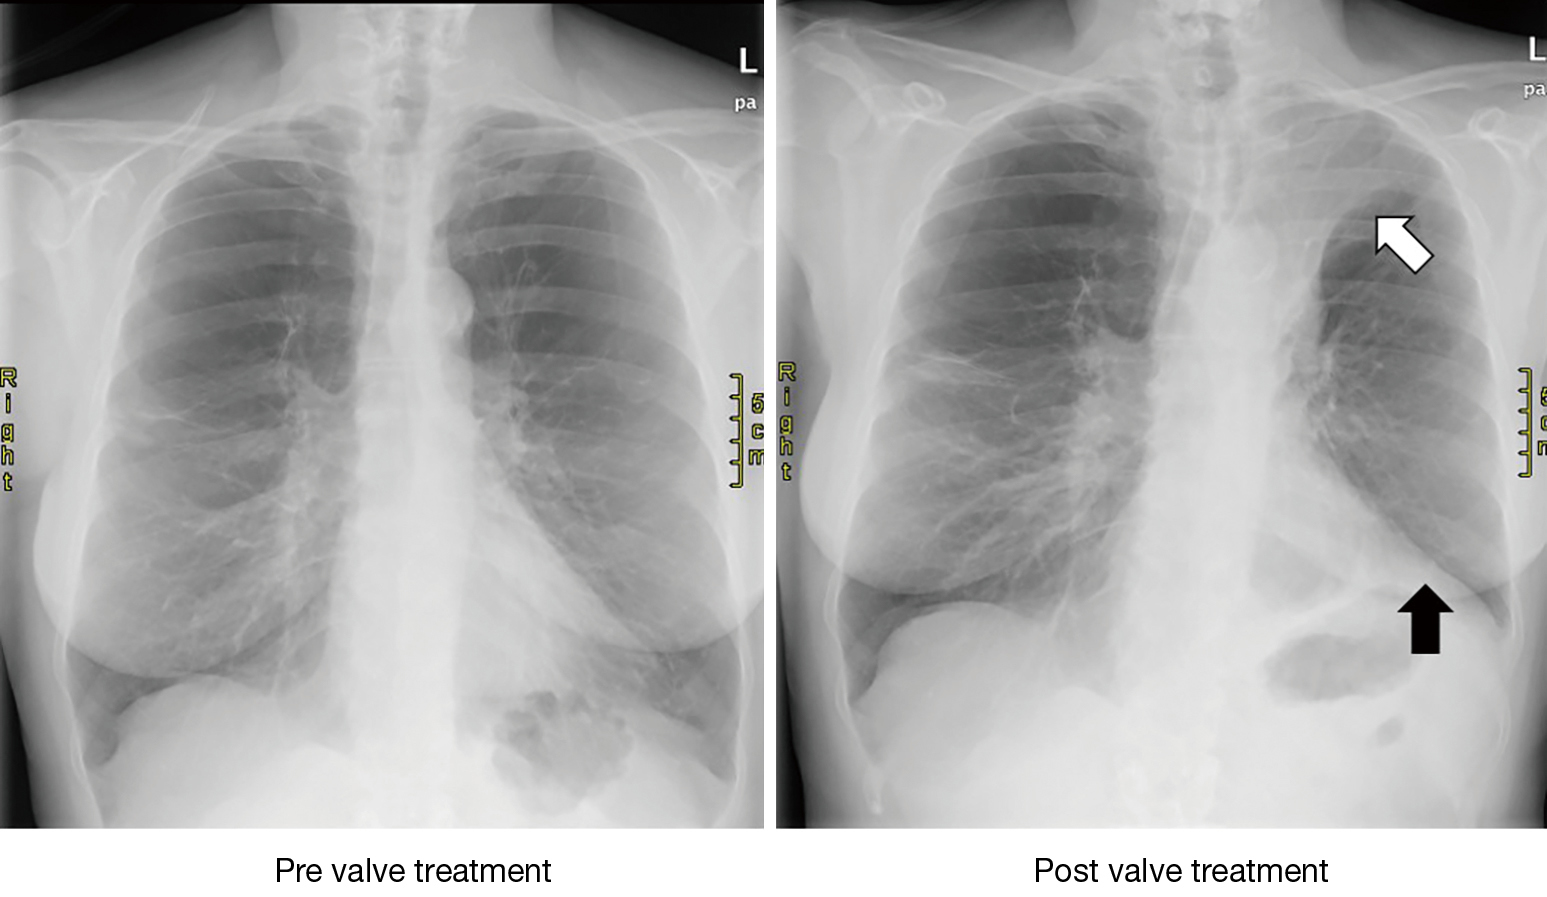

Bronchoscopic Lung Volume Reduction Using Endobronchial Valves Imaging Lung Valves For Copd Michael viola, who developed copd after 9/11, underwent a minimally invasive procedure at duke health that improved his lung function and breathing. Learn how zephyr valves can improve lung function, exercise capacity and quality of life for severe emphysema patients. Zephyr valves are devices that block off the damaged parts of the lungs and reroute airflow to the healthy ones.. Lung Valves For Copd.